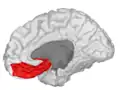

Orbital gyrus shown in red -

Basal surface of cerebrum. Orbital gyrus shown in red. -